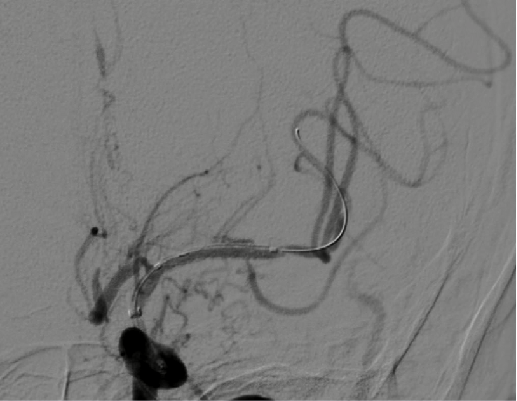

导引导管到位,导丝通过病变。

导丝怎么扩【载药时代 球扩天下】NOVA DES®颅内药物洗脱支架在颅内富穿支区域使用体会二例!_https://www.jmylbn.com_新闻资讯_第14张

导丝怎么扩【载药时代 球扩天下】NOVA DES®颅内药物洗脱支架在颅内富穿支区域使用体会二例!_https://www.jmylbn.com_新闻资讯_第15张

球囊扩张后。

导丝怎么扩【载药时代 球扩天下】NOVA DES®颅内药物洗脱支架在颅内富穿支区域使用体会二例!_https://www.jmylbn.com_新闻资讯_第16张

导丝怎么扩【载药时代 球扩天下】NOVA DES®颅内药物洗脱支架在颅内富穿支区域使用体会二例!_https://www.jmylbn.com_新闻资讯_第17张

支架通过病变。